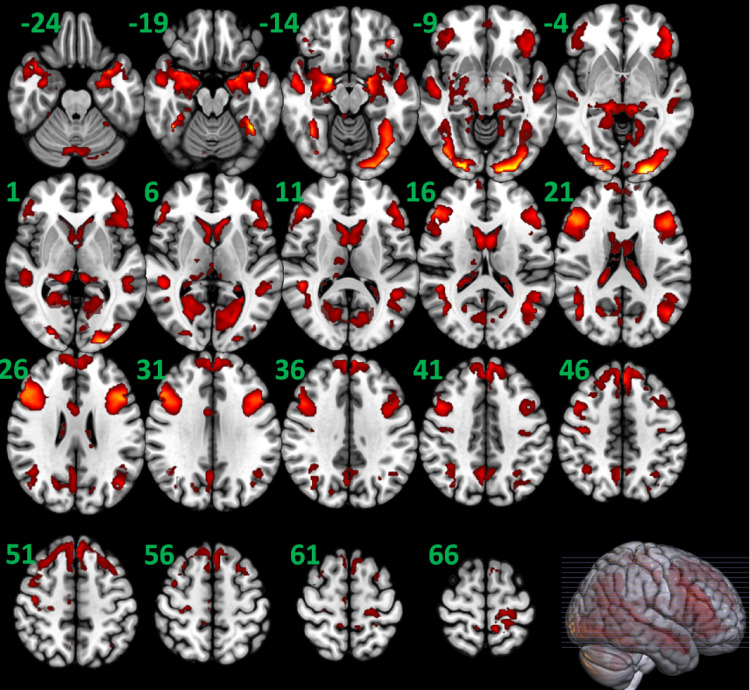

情绪调节障碍和情绪症状与酒精使用障碍(AUD)风险相关,但其中潜在的异常神经回路尚不清楚。在本研究中,我们研究了患有和不患有AUD的个体在情绪面部加工过程中有效(定向)连接(EC)的变化。我们利用了70名AUD参与者和70名对照组(CON)在情绪面部处理任务中获得的人类连接组项目的功能性MRI数据。以腹内侧前额叶皮层(VMPFC)、双侧腹外侧前额叶皮层(VLPFC)、杏仁核(AMY)、梭状回(FG)和右下丘脑(HTN)节点为研究对象,我们进行了动态因果模型分析,以检验EC在组水平上的差异。线性回归表征了EC与累积酒精暴露、抑郁和焦虑的关系。与CON组相比,AUD组从VMPFC→双侧VLPFC、左(L)-VLPFC→L-VLPFC和VMPFC、R-VLPFC→L- fg、R-FG→HTN和R-AMY→L-VLPFC的ECs较低;VMPFC→VMPFC, L-VLPFC→R-VLPFC和双侧FG, L-FG→R-AMY和HTN, R-AMY→VMPFC和L-FG,以及L-AMY→HTN连接产生更大的ECs。在回归分析中,这些皮层到皮层和皮层到皮层下的ECs与累积酒精暴露有关。从R-VLPFC到L-FG的EC与抑郁呈负相关。患有AUD的个体在控制情绪控制的大脑区域的情绪面部处理过程中,皮层到皮层和皮层到皮层下回路的EC被破坏,这可能解释了累积酒精暴露与抑郁之间的联系。

Impairments in emotional regulation and mood symptoms are interrelated and associated with alcohol use disorder (AUD) risk, but the underlying aberrant neural circuitry involved is poorly understood. In the present study, we examined alterations in effective (directional) connectivity (EC) during emotional face processing in individuals with and without AUD. We utilized functional MRI data from the Human Connectome Project obtained during an emotional face processing task in 70 participants with AUD and 70 controls (CON). Focusing on ventromedial prefrontal cortex (VMPFC), bilateral ventrolateral prefrontal cortex (VLPFC), amygdala (AMY), and fusiform gyrus (FG), and right (R) hypothalamus (HTN) nodes, we performed dynamic causal modeling analysis to test group-level differences in EC. Linear regressions characterized EC relationships with measures of cumulative alcohol exposure and depression and anxiety. Compared to CON participants, AUD participants had lower ECs from VMPFC → bilateral VLPFC, left (L)-VLPFC → L-VLPFC and VMPFC, R-VLPFC → L-FG, R-FG → HTN, and R-AMY → L-VLPFC; and greater ECs from VMPFC → VMPFC, L-VLPFC → R-VLPFC and bilateral FG, L-FG → R-AMY and HTN, R-AMY → VMPFC and L-FG, and L-AMY → HTN connectivities. In regression analyses, these cortical-to-cortical and cortical-to-subcortical ECs were associated with cumulative alcohol exposure. EC from R-VLPFC to L-FG was negatively associated with depression. Individuals with AUD have disrupted EC in cortical-to-cortical and cortical-to-subcortical circuits during emotional face processing in brain regions purported to govern emotion control, which may explain linkages between cumulative alcohol exposure and depression.